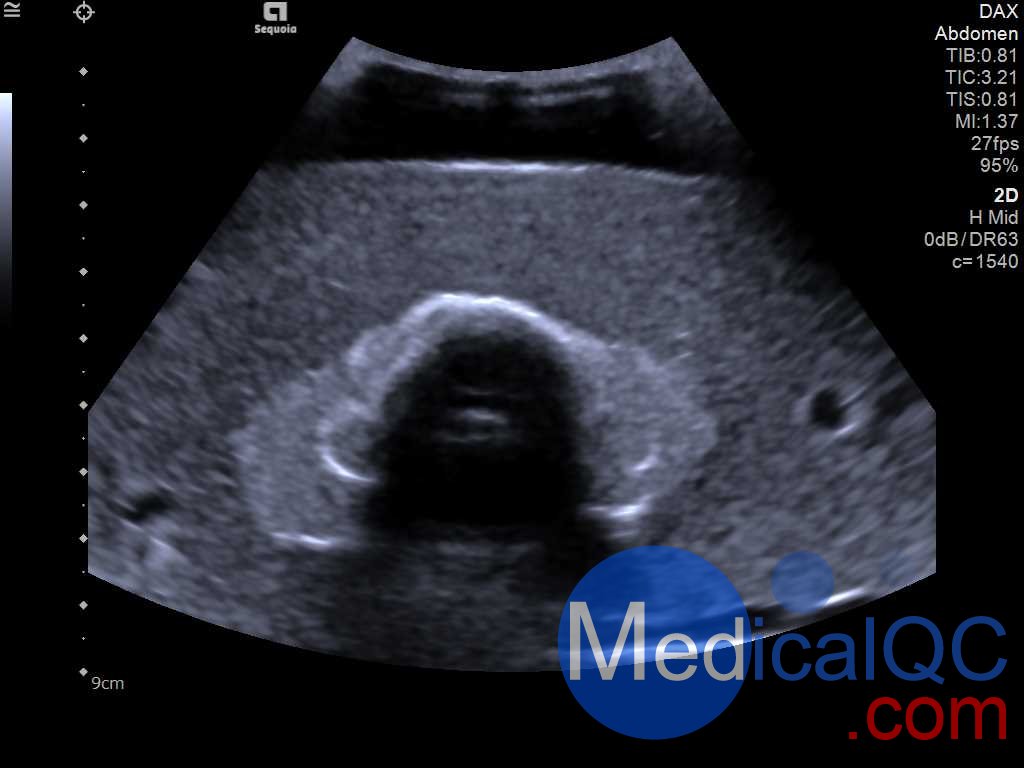

Cirs 074模体包含一个略微增大的甲状腺,位于拟人化的脖子内。下巴和锁骨作为外部解剖标志。模体提供气管、颈内静脉和颈总动脉作为内部解剖标志。每个甲状腺叶包含一个囊肿和一个等回声硬性病变。可以在甲状腺内定制制造各种结节。所有材料都经过精心设计,具有超声波逼真性。